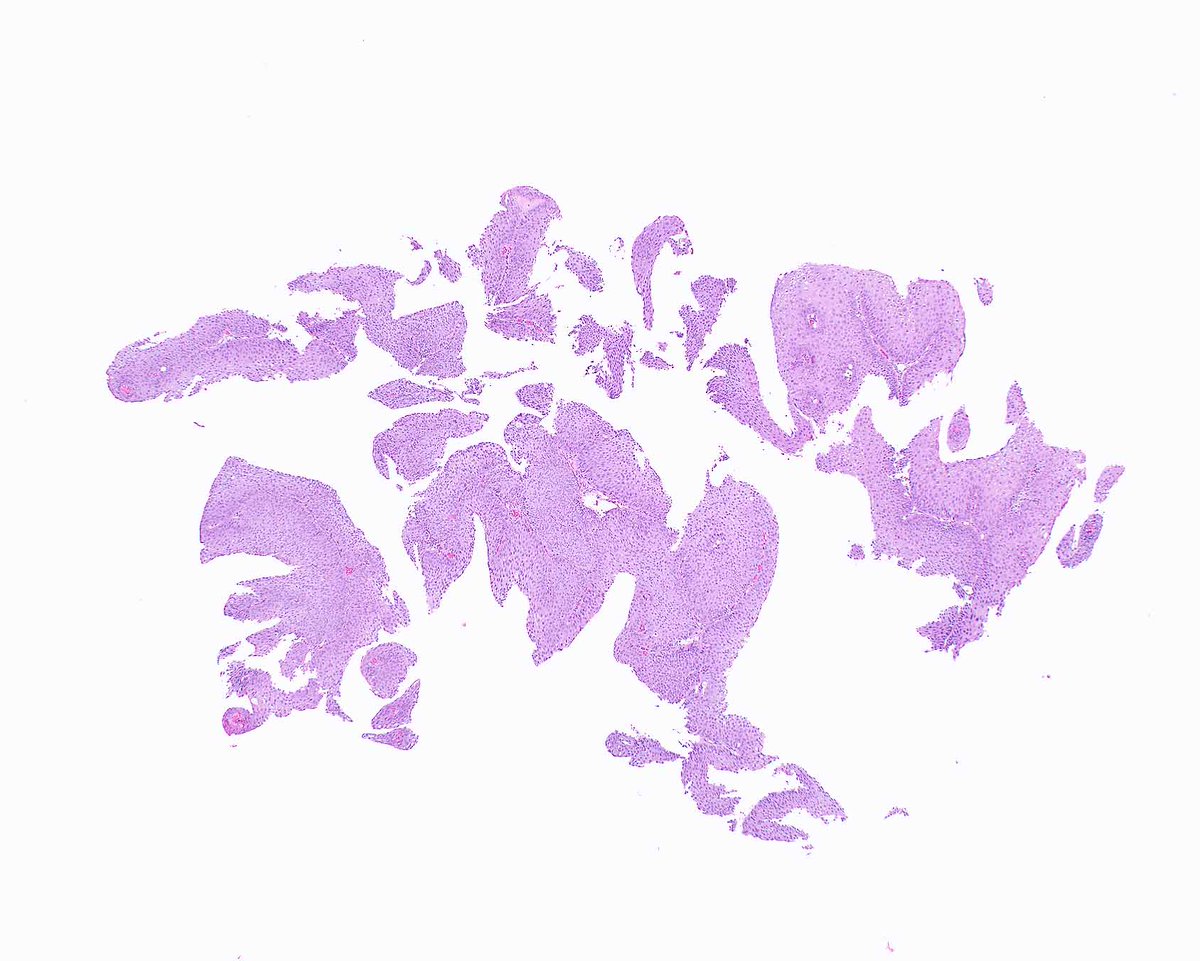

Our GI Pathology Fellowship has an unexpected opening for July 2026. Dr. Ortiz (right) and I are the program directors. We have superb cases and excellent colleagues (Drs. M. Garcia, R. Yantiss, S. Al Diffalha, O. McDonald). Send your CV to adriana.zanaty@miami.edu